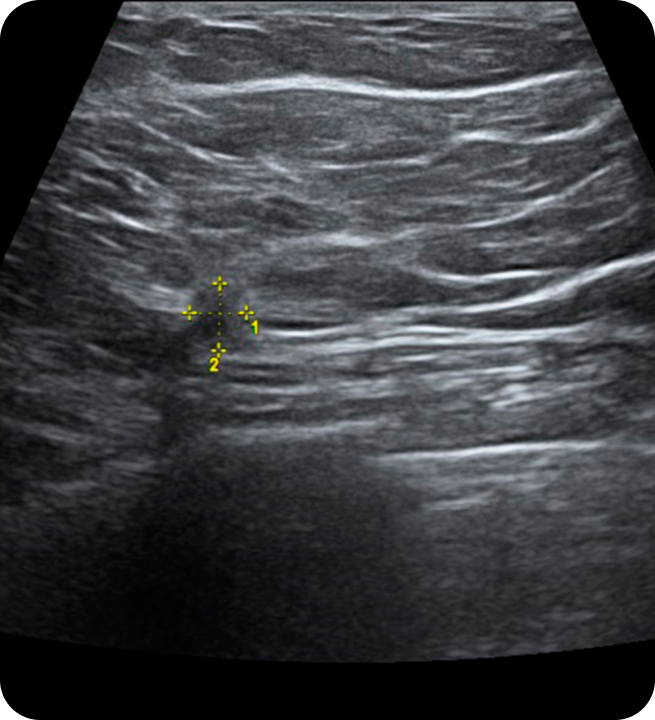

초음파 검사